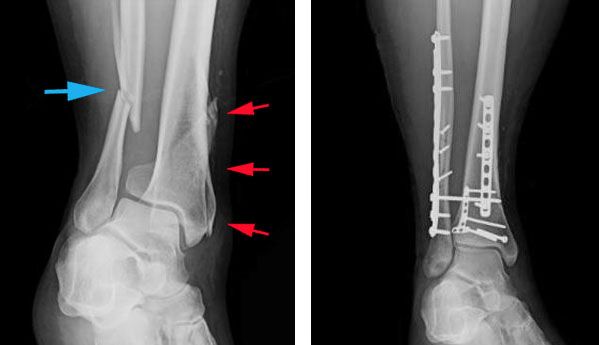

(Left) X-ray shows a fibula fracture (blue arrow) and a tibial shaft fracture (red arrows) that extends into the ankle joint. (Right) Both fractures have been treated with plates and screws.